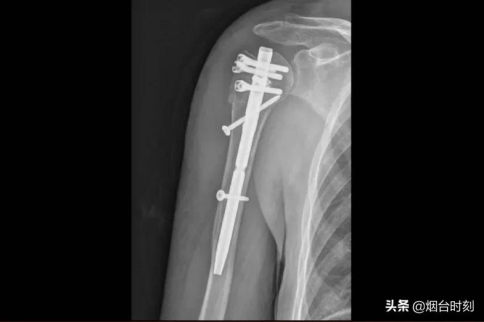

術(shù)前,將患者骨折部位的薄層CT掃描影像學(xué)信息進行三維重建,據(jù)此打印出骨折模型。手術(shù)時,醫(yī)師根據(jù)術(shù)前設(shè)計,有條不紊地展開手術(shù),將肱骨髓內(nèi)針植入。術(shù)后,患者的肩關(guān)節(jié)性能常態(tài),修復(fù)優(yōu)良,到達了之前預(yù)料的創(chuàng)傷小、修復(fù)快并且減小圍術(shù)期并發(fā)癥等目標(biāo)。

患者的術(shù)后影像。